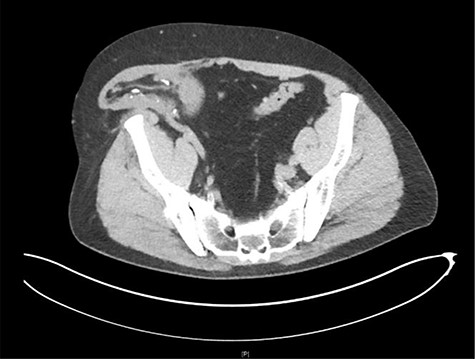

His workup was included but not limited to basic labs (CBC, CMP and UA), a renal transplant ultrasound, and a CT of the abdomen and pelvis. The CT scan revealed herniation of the right-sided donor kidney through an incisional hernia (Figs 1 and 2).

Axial view CT: herniation of the transplanted kidney through the right abdominal wall.